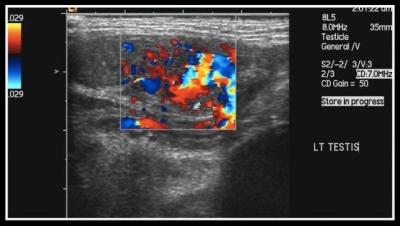

Figure 1: Ultrasound of the left testis which demonstrates an increase in doppler signal within the testis. The left testis is in the inguinal canal.